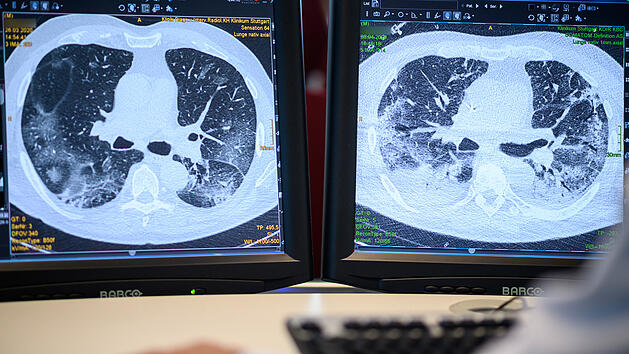

MünnerstadtCoronaEine der wenigen Kliniken: Behandlung von Long-Covid-Patienten in Unterfranken - das ist bekanntDie Kenntnisse über Long-Covid-Folgen sind bisher noch rar. Das Thoraxzentrum im unterfränkischen Münnerstadt behandelt als eine der wenigen Kliniken Patienten mit Corona-Spätfolgen. Welche neuen Erkenntnisse hat die Klinik und welche Therapiemethoden werden angewandt? 21.05.2021